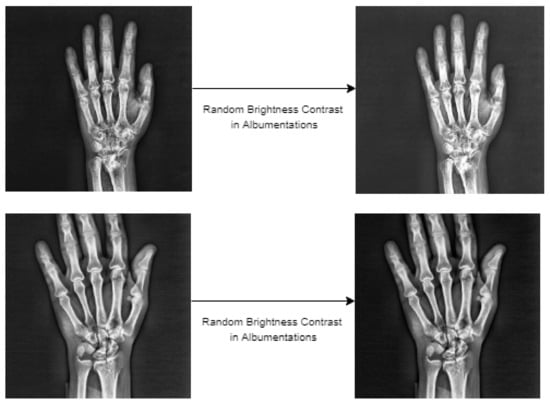

4.3. Data Augmentation of Wrist X-ray Images

The amount of data is essential for network training with deep-learning-based object detection models. Therefore, data augmentation was performed within the scope of this study in order to make the best of network training and to achieve high scores for fracture detection. As for the initial dataset, various augmentations were tried using the Albumentations [37] library. Albumentations is a flexible and fast image augmentation python library that can be used in different computer vision tasks that include object detection, classification and segmentation, which are particularly deep-learning-based open source projects [37]. In augmentations performed using this library, random brightness contrast, sharpness, noise, gamma, gaussian blur and median blur were used. Experiments of augmentation were conducted using these six different methods used in these procedures, either individually or together. Upon analysis of the detection procedures performed with augmentation, methods that have a negative impact on the result of detection, methods with no impact or the methods inclined to augmentation were identified. Based on the experiments, it was concluded that random brightness contrast augmentation made the greatest contribution for detection of fractures in the Albumentations library. This type of augmentation was used in addition to the random flip ratio 0.5 augmentation available in the training stage of the models in the MMdetection tool used for detection. Samples of the images obtained as the result of the augmentation steps are presented in Figure 12 below.

Figure 12.

The wrist X-ray images after data augmentation.